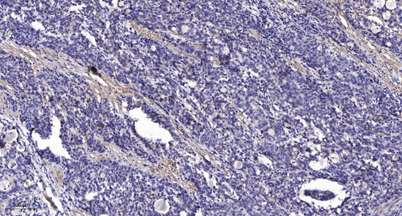

Product name: KV1.5 rabbit pAb

Dilutions: WB 1:500-2000;IHC-p 1:50-300; ELISA 2000-20000